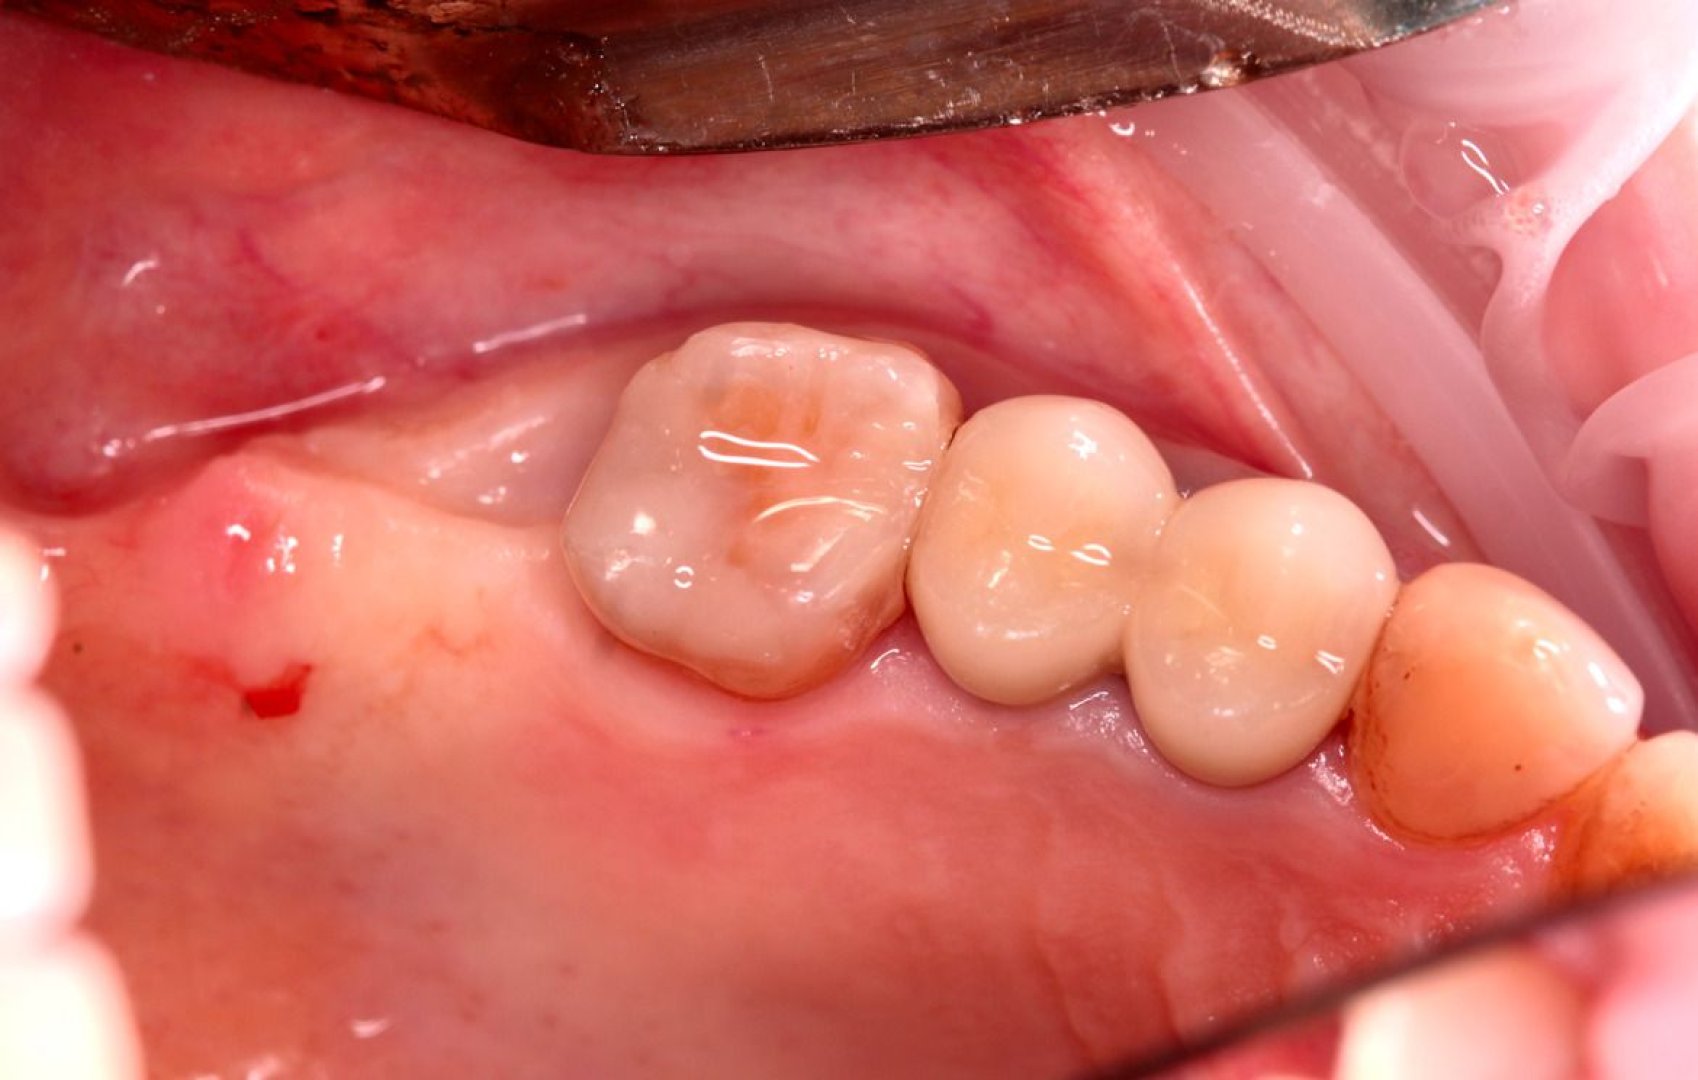

Хирургический 3D-шаблон для имплантации: планирование установки имплантов

Необходимость восстановления отсутствующих зубов с помощью имплантации. Требовалось максимально точное и безопасное позиционирование имплантов в костной ткани для долгосрочного прогноза и эстетики.